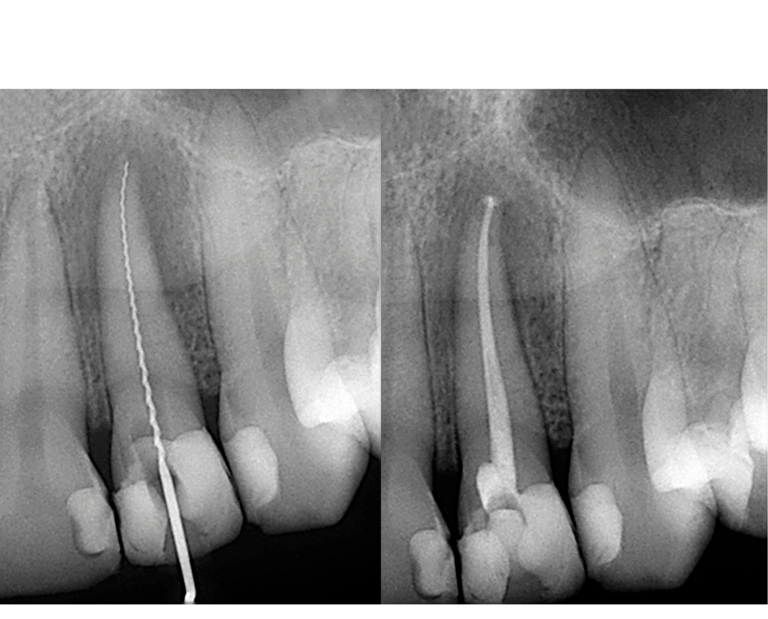

Endoncias

Limpieza y sellado del conducto radicular para eliminar infecciones y salvar el diente.

¿Qué es la endodoncia?

Es un tratamiento de conducto es un procedimiento en el que se elimina el tejido dañado o infectado del interior de un diente y se rellena con un material especial para evitar futuras infecciones.